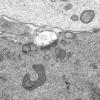

Neuroaxonal dystrophy (3)